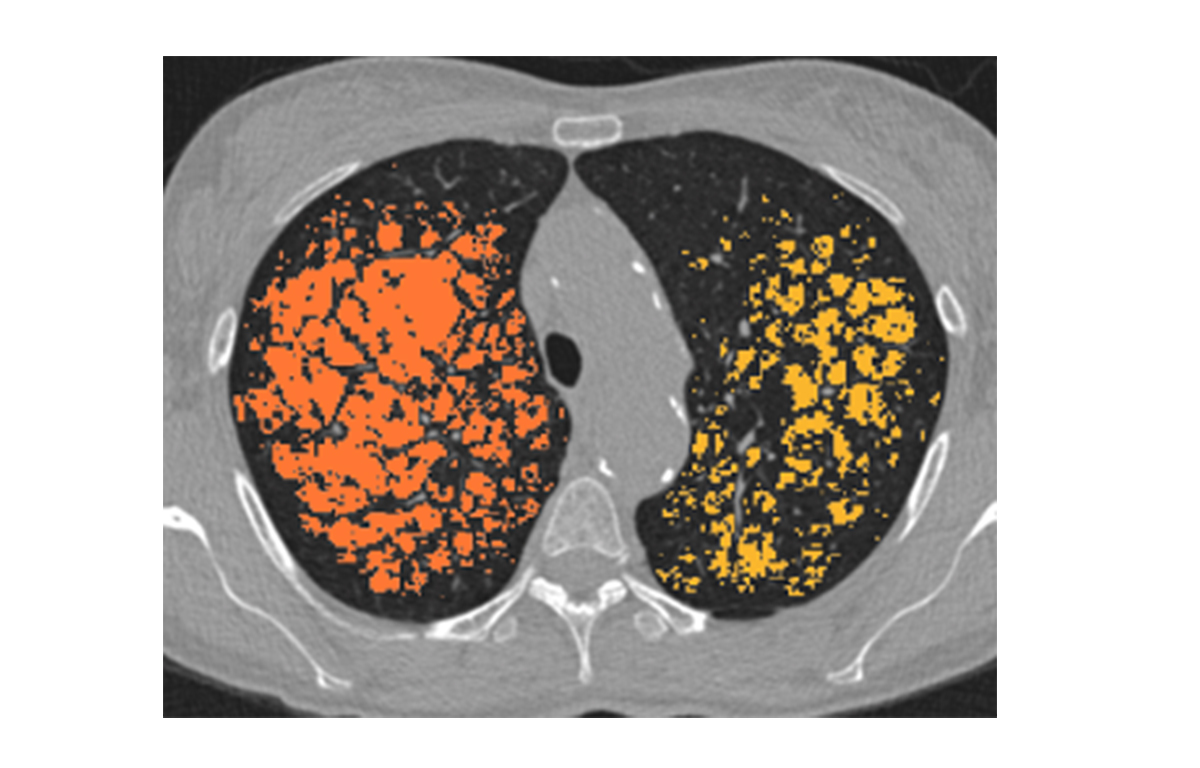

Built on advanced capabilities in lung segmentation and quantification, our AI technology interprets thoracic CT data with anatomical precision - capturing airway trees, parenchymal patterns, and vascular structures, even in severely diseased lungs.

- Quantitative analysis of complex lung patterns and diseased regions

Emphysema / Hyperinflation

- BLVR Implants

- Parenchymal Ablation

- Surgical Tissue Resection